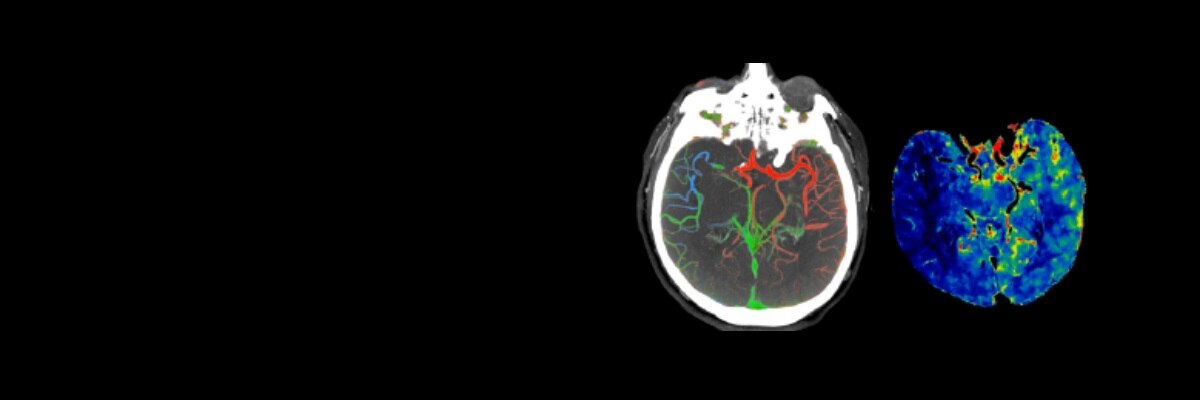

CT